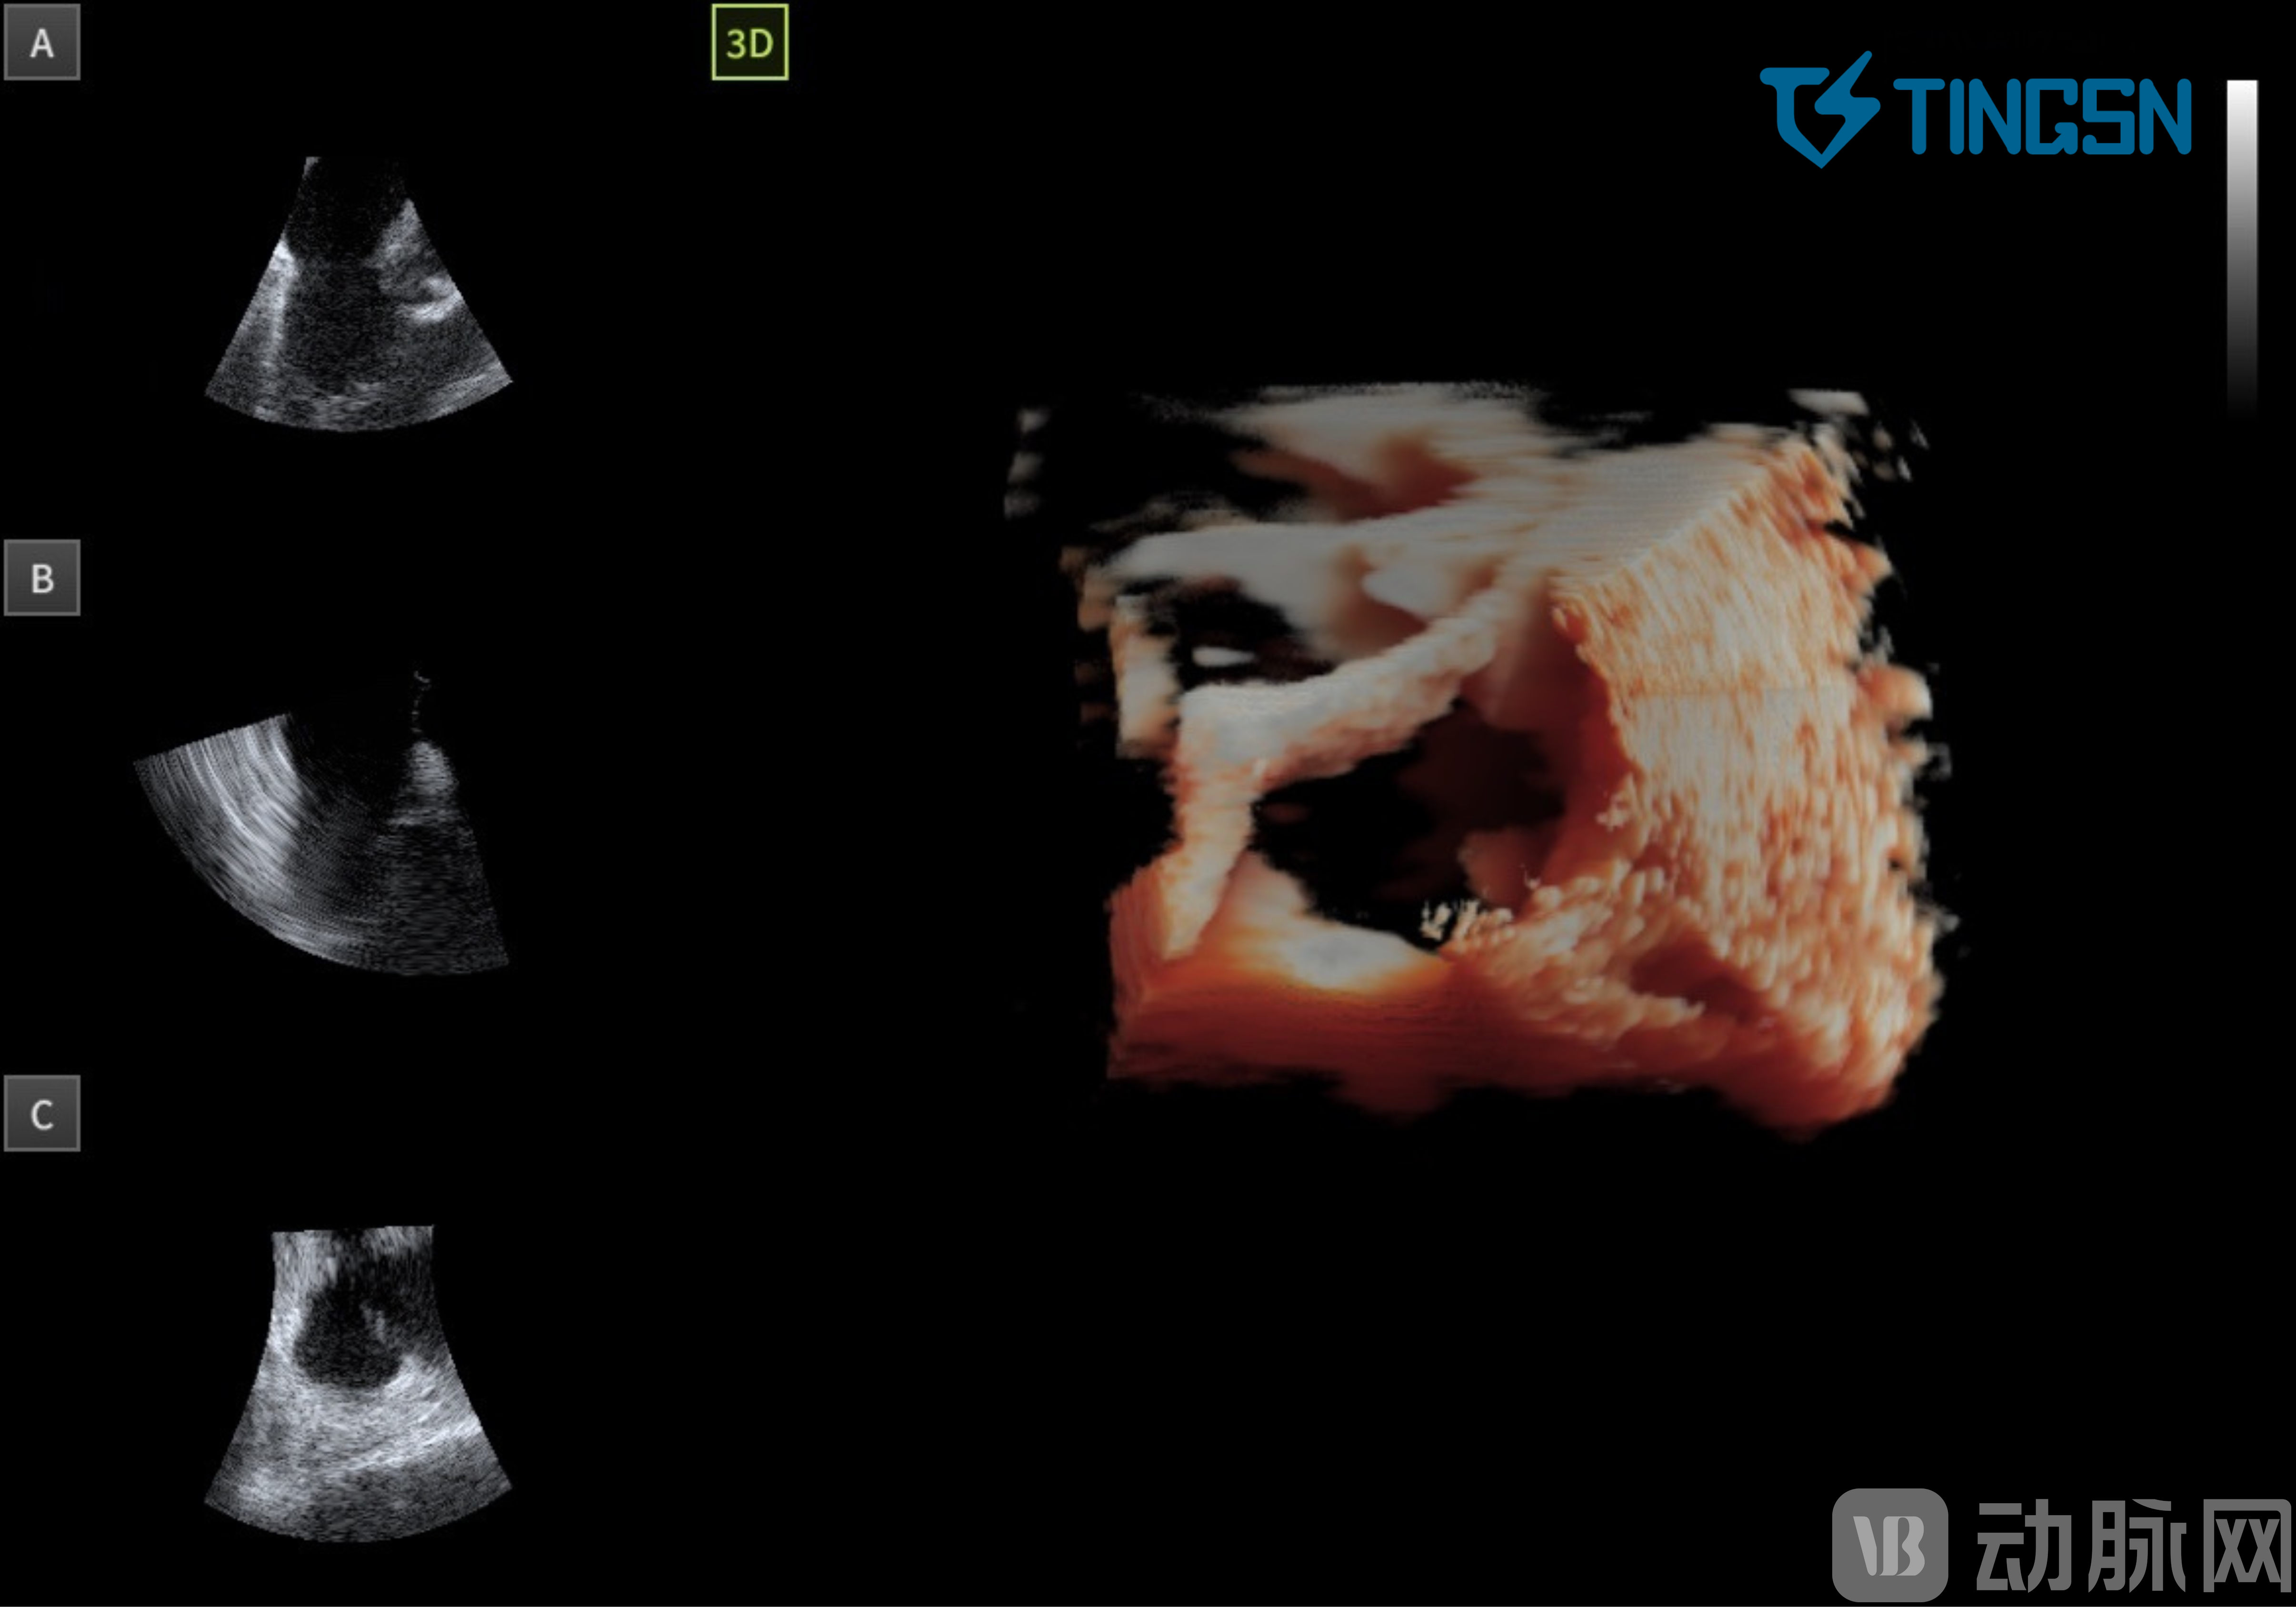

此种背景下,基于ASIC 芯片的 4D ICE 临床应用价值正在逐步被证实和加强。4D ICE 既可运用于 2D ICE 的所有手术场景,又可以在 2D ICE 无法解决的手术场景上进行精准的影像指导。4D ICE为临床医生提供的心脏实时三维立体的影像,会给产业带来全新的发展视角,真正从二维走向实时三维。

(实时三维立体影像,心室舒张期三尖瓣瓣叶呈开放状态)

从海外发展来看,目前 4D ICE 主要应用在左心耳封堵、二尖瓣修复手术、三尖瓣修复手术、经导管主动脉瓣置换手术、房颤射频消融手术、PFA 消融手术、冷冻消融手术、复杂的先天性心脏病手术等。